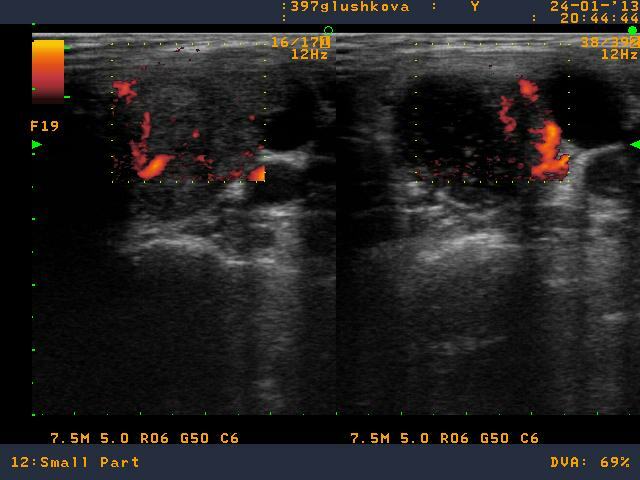

В Северо-Западном региональном эндокринологическом центре выполнена тонкоигольная аспирационная биопсия узла левой доли щитовидной железы. По результату биопсии щитовидной железы выявлена "Папиллярная карцинома щитовидной железы". Пациентке предложена операция, удаление левой доли щитовидной железы.